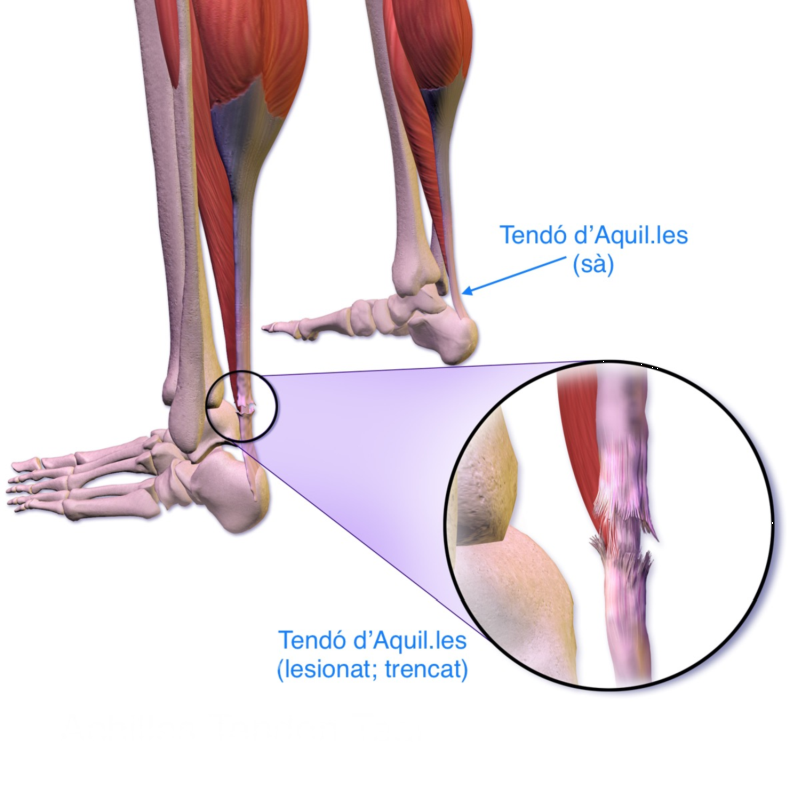

El tendó d'Aquil·les

El tendó d’Aquil·les uneix el múscul tríceps sural amb l’os calcani del tars del peu i permet la flexió plantar, i és indispensable per a la marxa.

Font: Wikipedia.